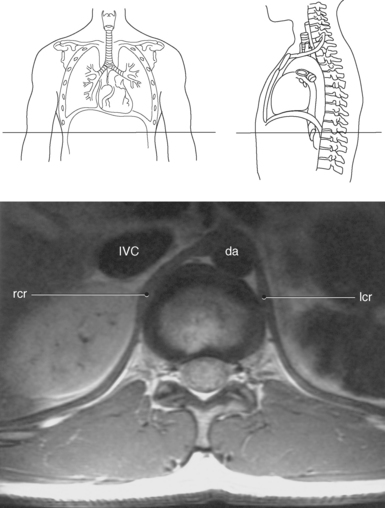

Muscles associated with respiration are the intercostal, serratus posterior superior, serratus posterior inferior, and the diaphragm (Table 6.3). The spaces between the ribs, or the intercostal spaces, are filled with three layers of intercostal muscles (external, internal, and innermost layer) (Figures 6.106 through 6.108). These muscles act together to elevate the ribs and expand the thoracic cavity, as well as keep the intercostal spaces somewhat rigid. The serratus posterior superior muscle spans from C7-T2 to ribs 2 to 5 and acts to assist forced inspiration, whereas the serratus posterior inferior muscle spans from T11-L2 to ribs 9 to 12 and acts to assist forced expiration (Figures 6.109 through 6.110). The diaphragm is a large dome-shaped muscle that spans the entire thoracic outlet and separates the thoracic cavity from the abdominal cavity (Figure 6.111). It is the chief muscle of inspiration because it enlarges the thoracic cavity vertically as the domes move inferiorly and flatten. The muscle fibers of the diaphragm converge to be inserted into a central tendon, which is situated near the center of the diaphragm immediately below the pericardium, with which it is partially blended. The diaphragm is attached to the lumbar spine via two tendinous structures termed crura (Figures 6.111 through 6.113). The right crus arises from the anterior surfaces of L1-L3, whereas the left crus arises from the corresponding parts of L1-L2 only. The left and right crura join together across the ventral aspect of the abdominal aorta to form the medial arcuate ligament. Three major openings, or hiatuses, of the diaphragm allow for the passage of vessels and organs from the thorax to the abdomen. The aortic hiatus allows for the passage of the descending aorta, azygos vein, and thoracic duct. The caval hiatus allows for the passage of the inferior vena cava and the right phrenic nerve. The esophageal hiatus allows for the passage of the esophagus and the vagus nerve.

Figure 6.112 Axial, T1-weighted MR scan of abdomen with crura.

Key: rcr, Right crus; IVC, inferior vena cava; da, descending aorta; lcr, left crus.